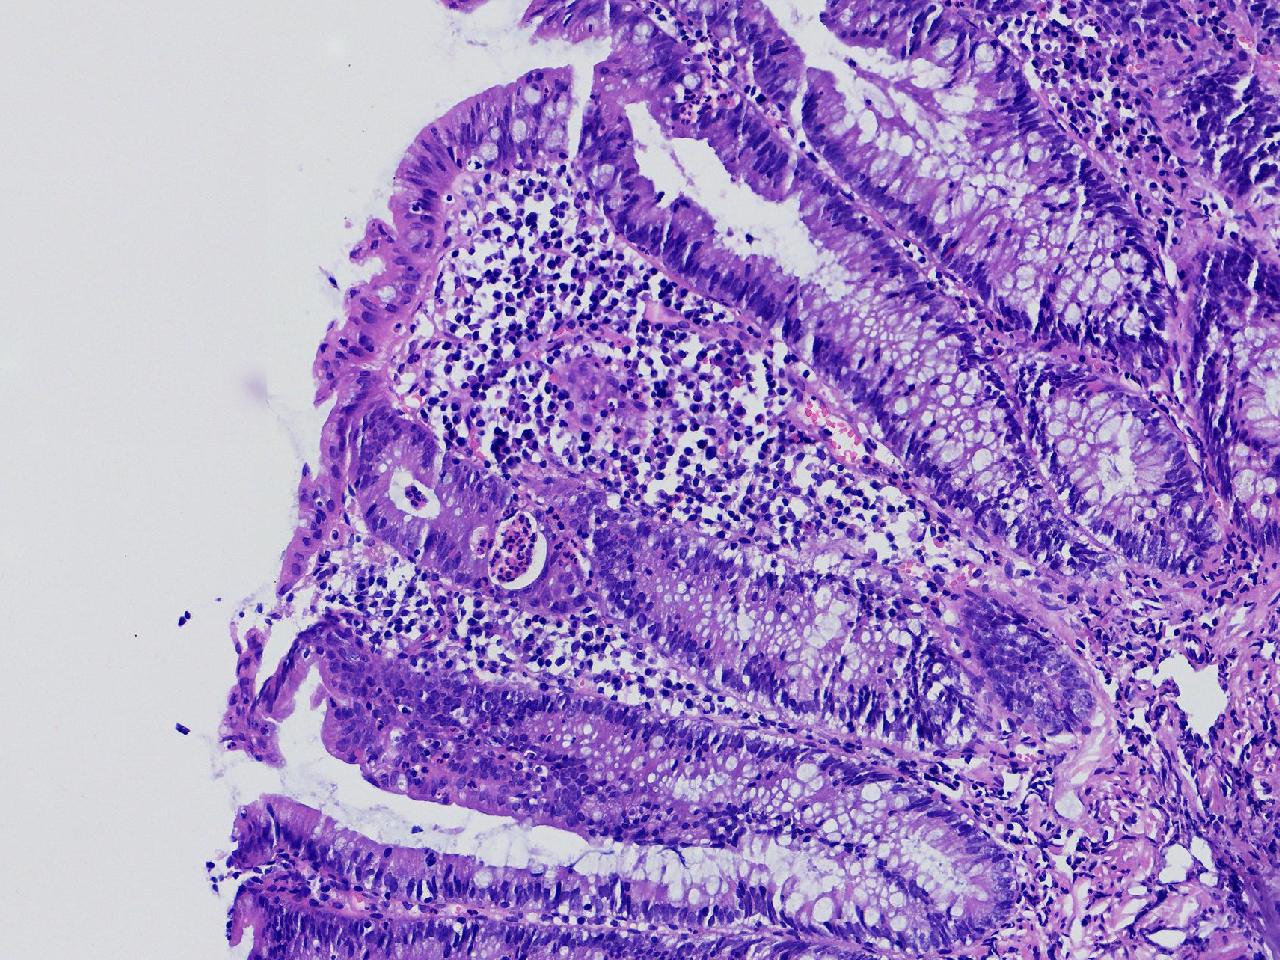

男,62岁,直肠见一直径约0.8cm大小的扁平隆起,表面光滑,活检1块。

直肠活检

灰白色不整形软组织1块,直径0.2厘米。

隐窝脓肿,杯状细胞减少,溃结考虑吗

炎症性肠病,溃结可能

不除外炎症性肠病,结合临床。